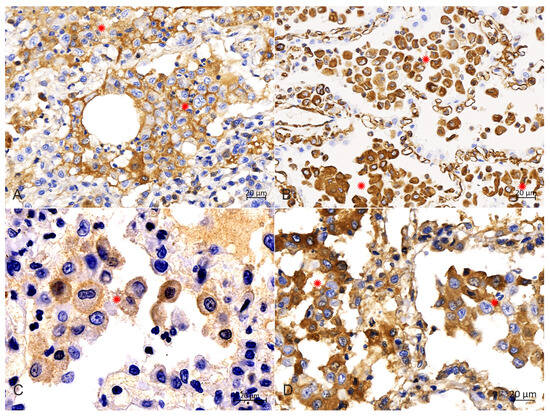

2.4. Immunohistochemistry

IHC analysis with diaminobenzidine staining and with all monoclonal antibodies (Abcarta) showed positive reactions for the monoclonal antibodies to CD1a (PA538; Figure 6A) in the membrane, and Vimentin (PA040; Figure 6B), S100 (PA139; Figure 6C) and E-cadherin (PA073; Figure 6D) in the cytoplasm of PHCs. Adverse reactions were observed for the monoclonal antibody to CD68. These data indicate that the PHCs were derived from LCs.

Diagnostic confirmation in cases of PLCH in humans and veterinary medicine depends on the IHC profile of histiocytic cells [3,6,8]. Langerhans cells are confirmed in tissues by their expression of CD1a, CD18, vimentin, E-cadherin, Iba-1, major histocompatibility complex class II molecules and langerin (CD207) [3,6,8,18]. Following previous reports of pulmonary LCH, the IHC analysis results in this study showed that the PHCs were strongly positive for CD1a, vimentin, S100 and E-cadherin, as well as negative for CD68, which supports an LC phenotype. The CD1a molecule is expressed exclusively by LCs; it could be used to confirm further the diagnosis of feline LCH, and its positive expression in the present study is consistent with an LC origin. Although some researchers purport that the availability and use of CD1a are limited because the antibody is not assessable in formalin-fixed tissues [6], Peter Moore et al. argued that its expression has been confirmed in frozen sections of lung lesions in a recent case [3]. Vimentin is overexpressed in various epithelial cancers [19], and S100 is widely reported to participate in multiple signaling pathways in tumor cells [20]. In our study, the positive expression of the two molecules in the PHCs could be considered as evidence in favor of neoplastic transformations. The adhesion molecule E-cadherin is mainly expressed by epithelial cells, but also by LCs, and LCs are the only histiocytic cells that express E-cadherin [5,8,10]. Given that E-cadherin immunolabeling has not been reported in other histiocytic disorders of canines and felines, its positivity is highly supportive of an LC origin [16,21]. Therefore, the positive result of our IHC labeling for E-cadherin, in association with those for CD1a, vimentin and S100, further confirms the diagnosis of an LC origin of lung histiocytosis. Furthermore, the myeloid marker CD68 is a protein highly expressed in circulating and tissue macrophages [22], and it is traditionally employed to immunostain monocytes/macrophages in the histochemical analysis of inflamed tissues and tumor tissues [23]. Therefore, in this study, the negative expression of this molecule in the PHCs indicated that the infiltrated cells could be ruled out as having a monocyte or macrophage origin.

Figure 6. Immunohistochemical analysis in the cytoplasm of PHCs. (A) Immunohistochemical staining of the CD1a was strongly positive in the membrane of PHCs (around asterisks), bar = 20 μm. (B) Immunohistochemical staining of vimentin was strongly positive in the cytoplasm of PHCs (around asterisks), bar = 20 μm. (C) Immunohistochemical staining of S100 was strongly positive in the intramembrane of PHCs (around asterisks), bar = 20 μm. (D) Immunohistochemical staining of E-cadherin was strongly positive in the cytoplasm of PHCs (around asterisks), bar = 20 μm.